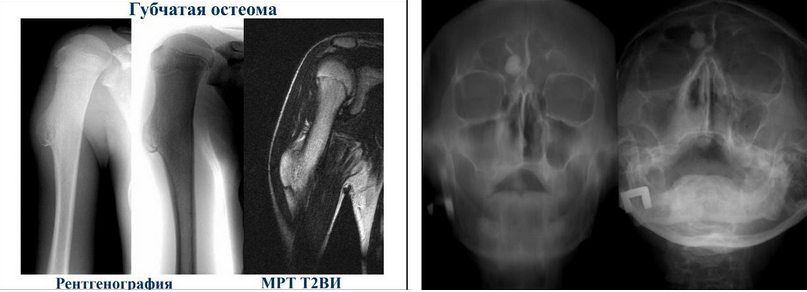

КТ околоносовых пазух. Что такое остеома?

Если остеома оказывает давление на окружающие структуры, могут понадобиться дополнительные исследования, такие как КТ или МРТ.